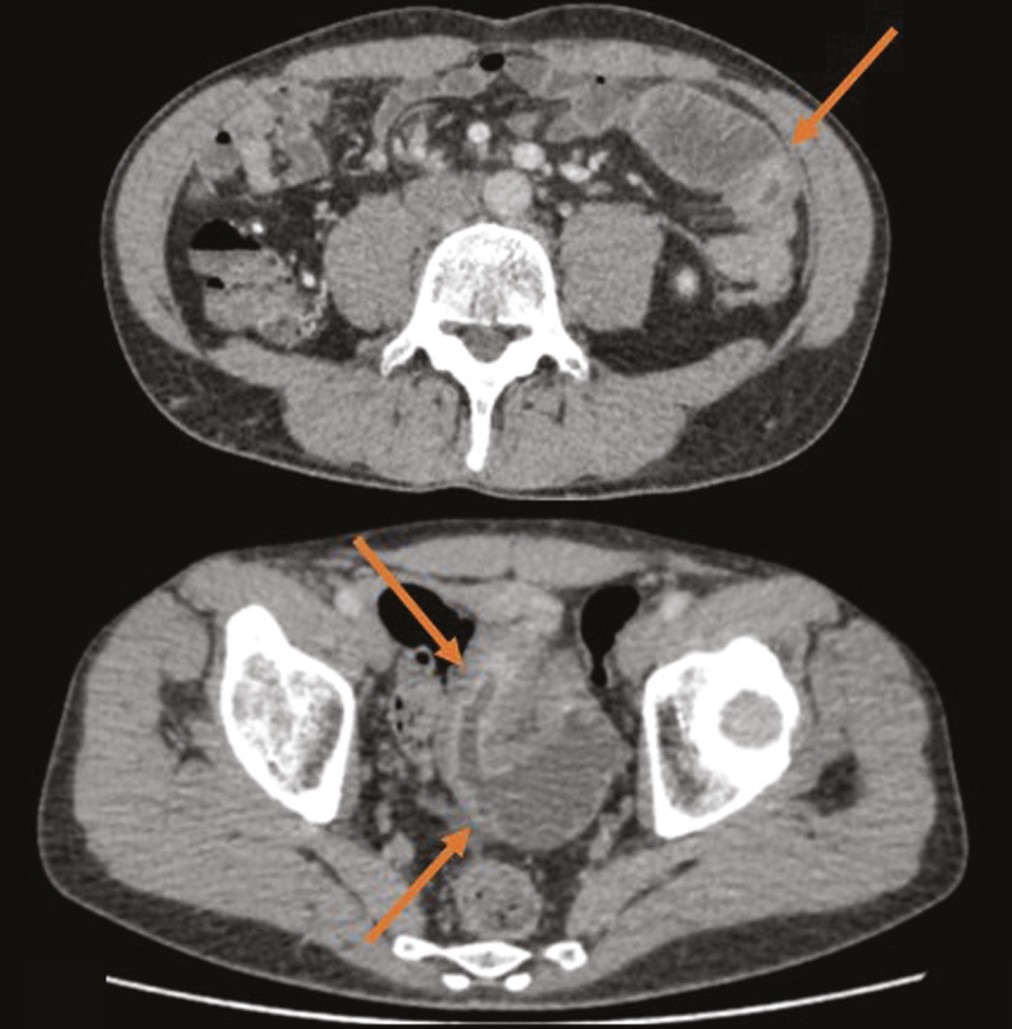

We present a clinical case of ambiguous clinical manifestations of Crohn’s disease with small intestine and rectal involvement. Tomographic imaging was used to confirm the diagnosis. A 44-year-old patient presented with complaints of non-pronounced abdominal pain, dyspepsia. The lab panel showed indirect signs of malabsorption, an increase in fecal calprotectin. An endoscopic examination with histological verification revealed a picture of proctitis. After performing computed tomography and/or magnetic resonance enterography multiple lesions of the small intestine were revealed. This clinical case demonstrates an atypical clinical picture of Crohn’s disease with jejunal, iliac, and rectal lesions.

The patient had no characteristic complaints; the results of endoscopic and morphological studies were not informative. Imaging by means of computed and magnetic resonance tomography has played a crucial role in the diagnosis and successful treatment.